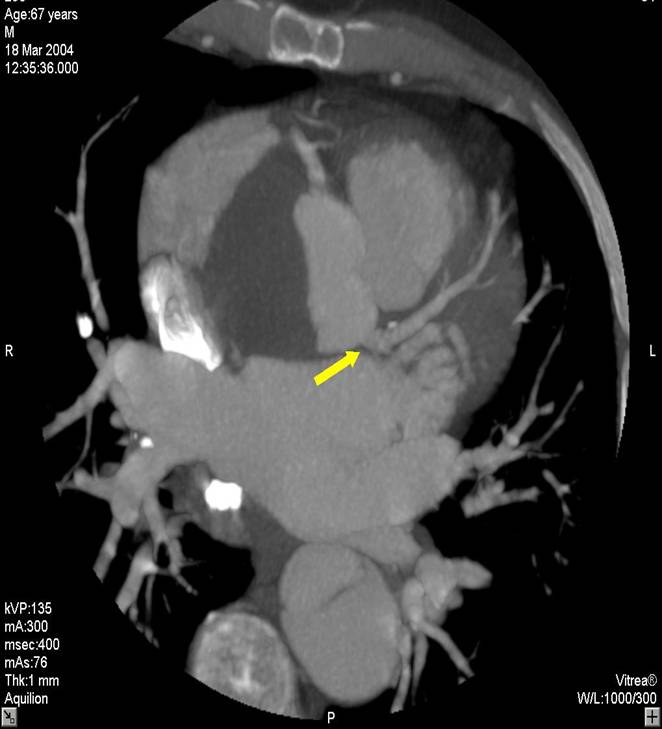

The non-invasive imaging modality of multi-detector computed tomography has dramatically evolved the last ten years and that is due to hardware and software developments. The newer generation of scanners allows increased spatial and temporal resolution that improves the clinical reliability giving further insights into the evaluation of coronary artery disease. Heart morphology imaging followed by studies of myocardial function and assessment of cardiac valves can be performed from the information derived from the data of the coronary artery examination. Also, the venous anatomy of the heart, coronary artery bypass grafts, stents, and cardiac tumors can be imaged and evaluated when necessary. For the beneficial use of this method, entrance criteria for different patient groups need to be set in order to allow improved outcome of multi-detector CT.